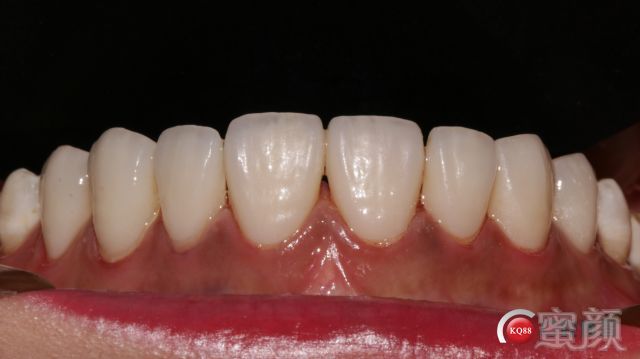

下颌我要等技工室的全合架到位了再做;因为涉及到几个合位关系的确定问题;下颌要采用对接式所以侧方合关系要特别注意,不然会出问题。患者很满意;中缝黑三角2周后应该可以恢复;排龈时间压得有点长;两单位对称粘接;邻间隙一定要能过牙线,再往下做;手术刀慢慢刮还是有点费力。效果不错患者满意。

两周后再拍一下效果和大家一起讨论。多多指教;没有对比就没有伤害;切端通透生长叶形态能表达出来;牙面纹路生动符合患者年龄的纵横纹的表达。面型笑线和牙体的协调。